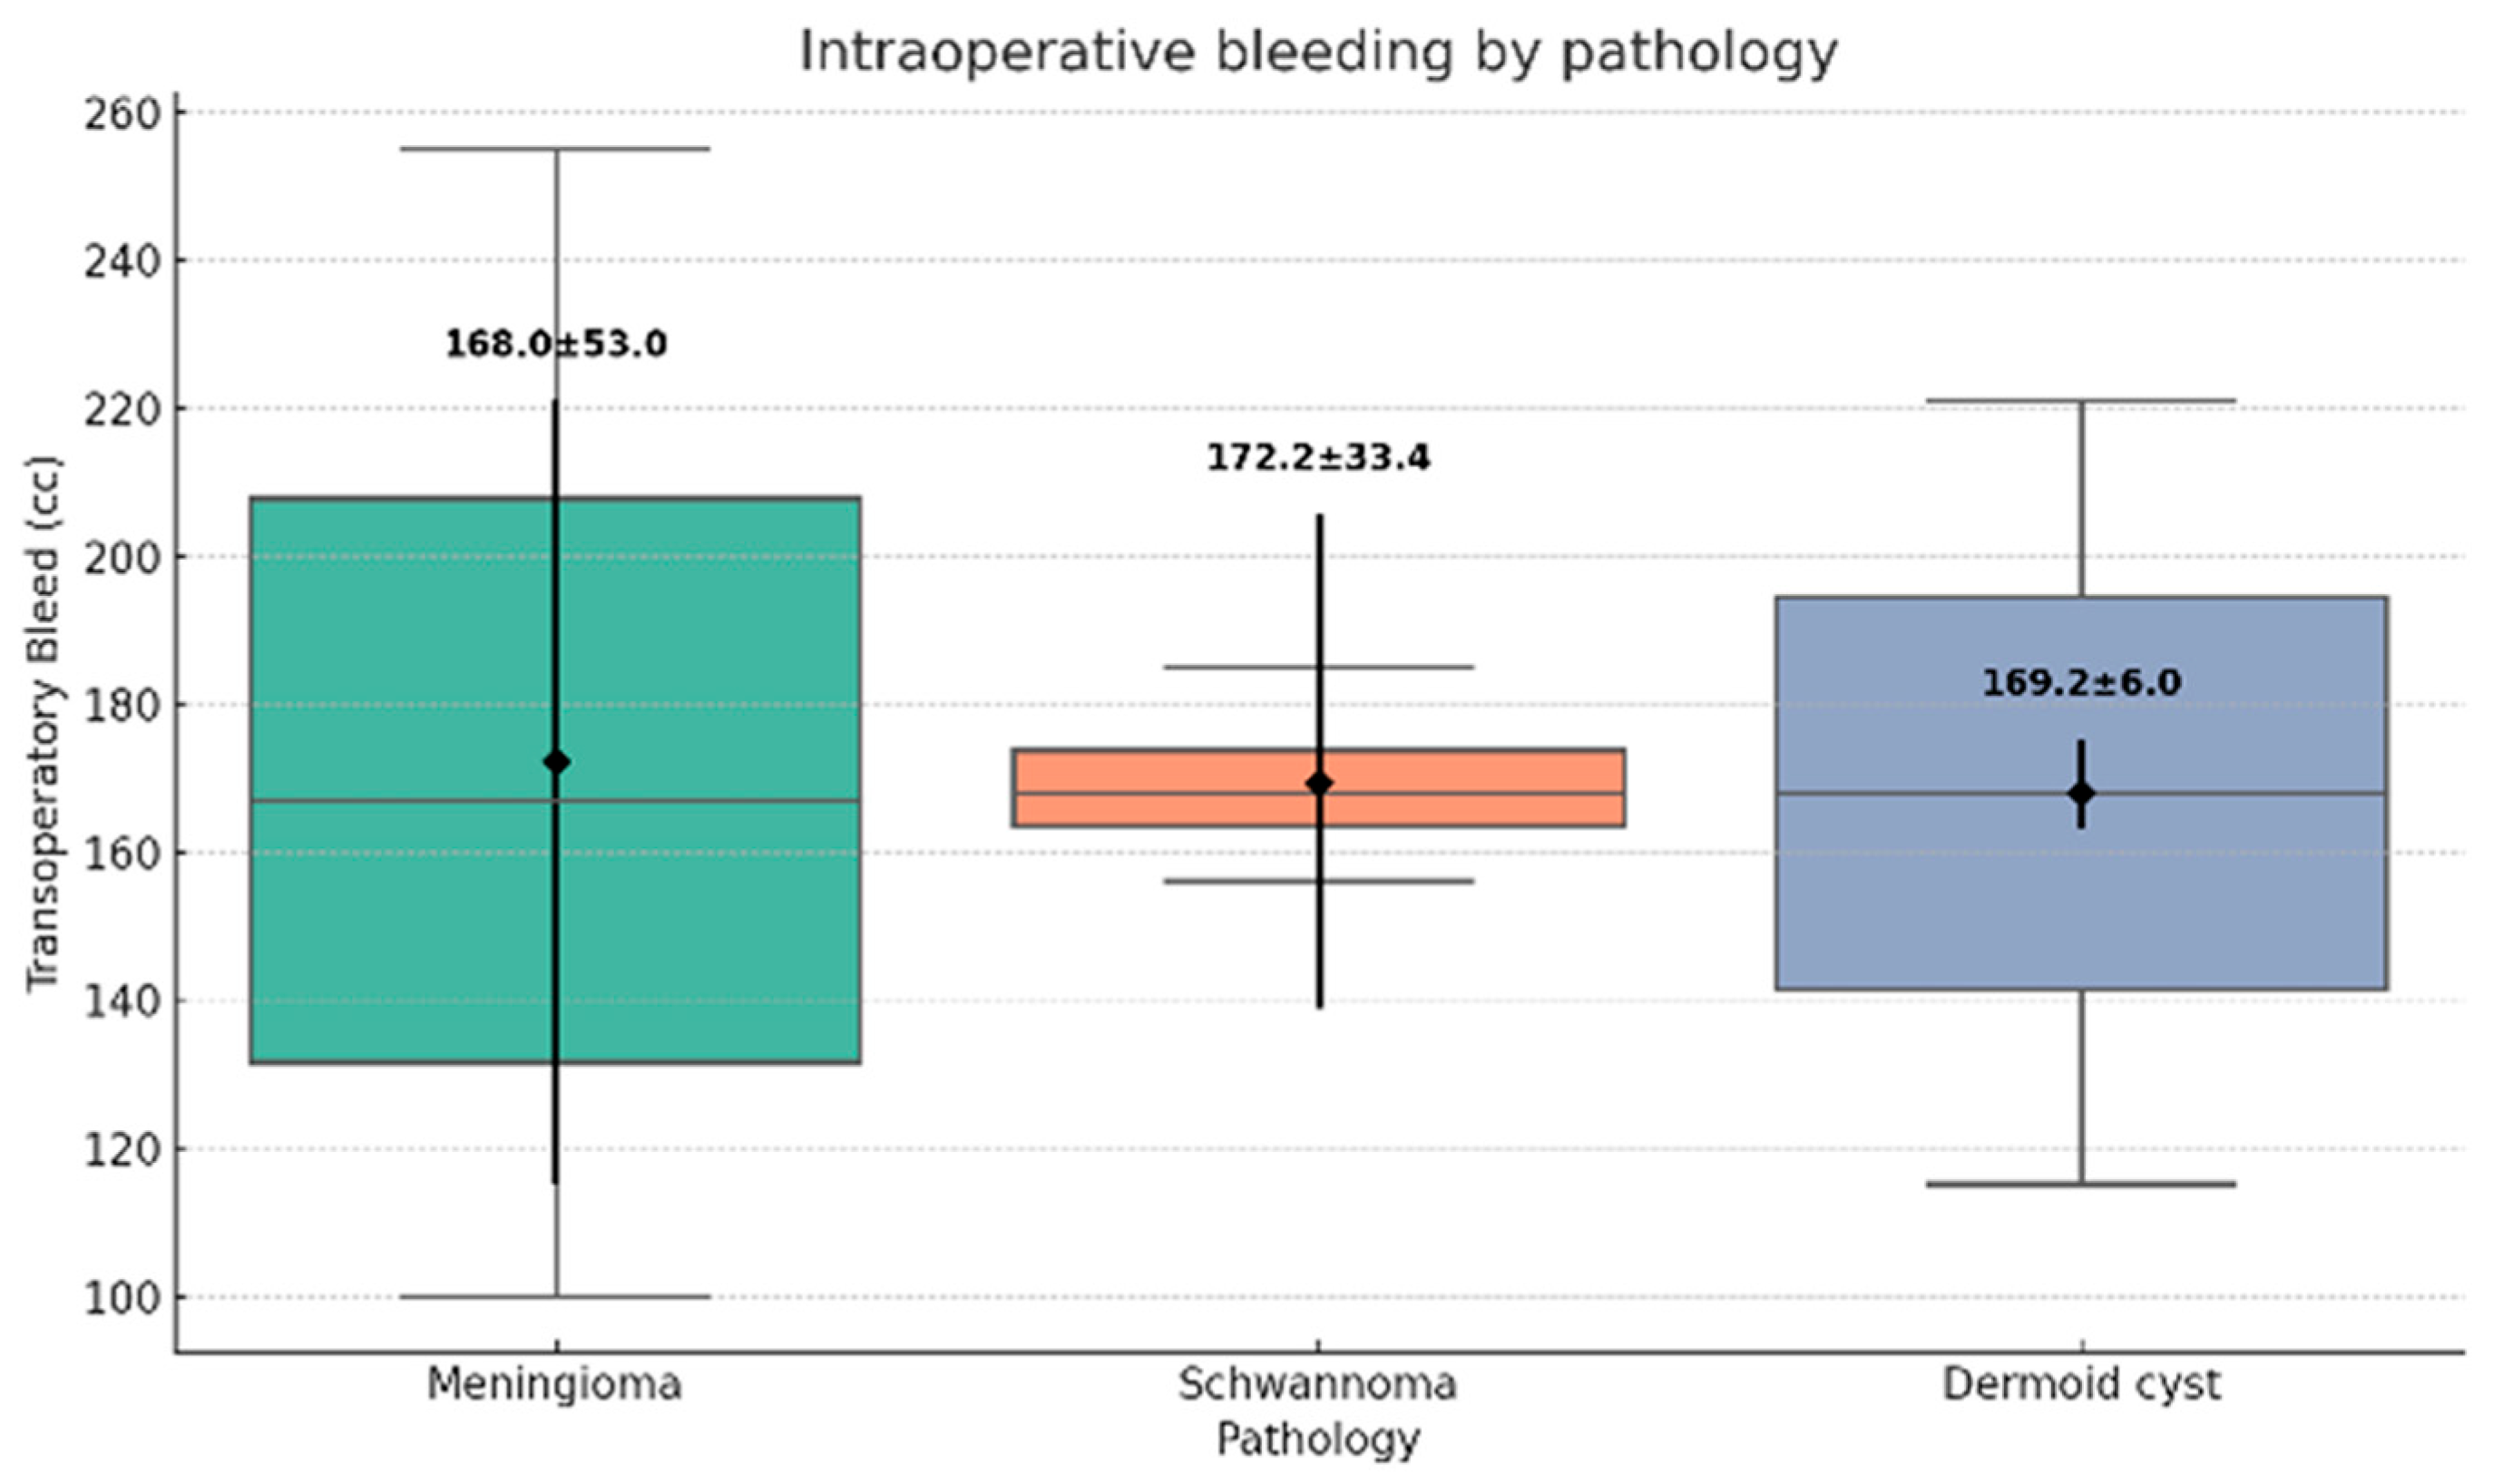

All surgical procedures were successfully completed via the UBE technique, with no conversions to open surgery. The mean operative time was 168.5 ± 24.3 min (range: 100–200 min) (

Figure 4). Estimated operative blood loss averaged 48.1 ± 12.7 mL (range: 30–70 mL) (

Figure 5).